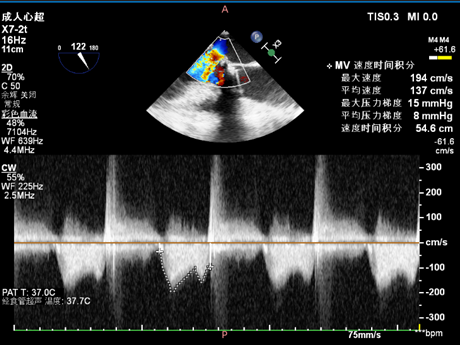

二尖瓣

术后

术前术后流速压差对比,术前最大速度265cm/s,平均速度189cm/s,最大压力梯度28mmHg,平均压力梯度16mmHg;术后最大速度194cm/s,平均速度137cm/s,最大压力梯度15mmHg,平均压力梯度8mmHg: